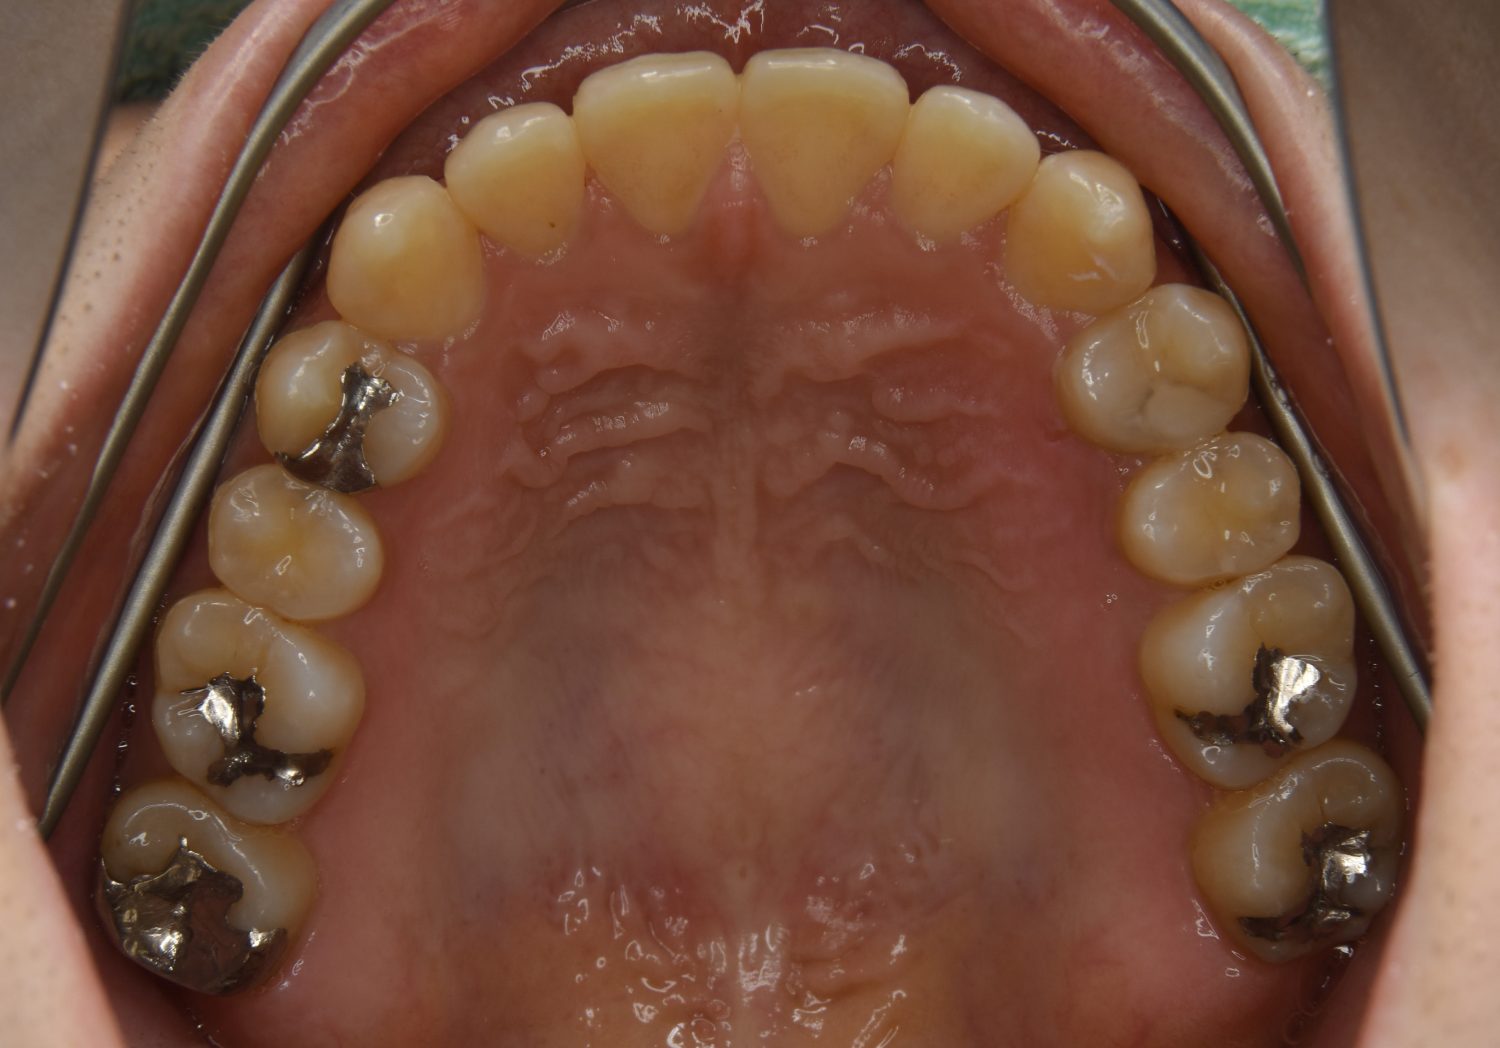

前歯部開咬の症例紹介①

Before

主訴

前歯が開いているのが気になる。

治療内容

上リンガルブラケット(舌側装置)、下ラビアルブラケット(唇側装置)に矯正用アンカースクリューを併用し非抜歯で治療を行いました。

治療費

1,200,000 円(税込)

治療期間

33ヶ月

通院回数

34回

想定されたリスク

※歯根吸収、歯肉退縮、歯髄壊死、顎関節症状

上下の前歯が開いており前歯では全く噛めていない状態でした。臼歯の圧下を行うことで前歯でも咬合できるようになり機能面のみでなく審美面も著しく改善しました。